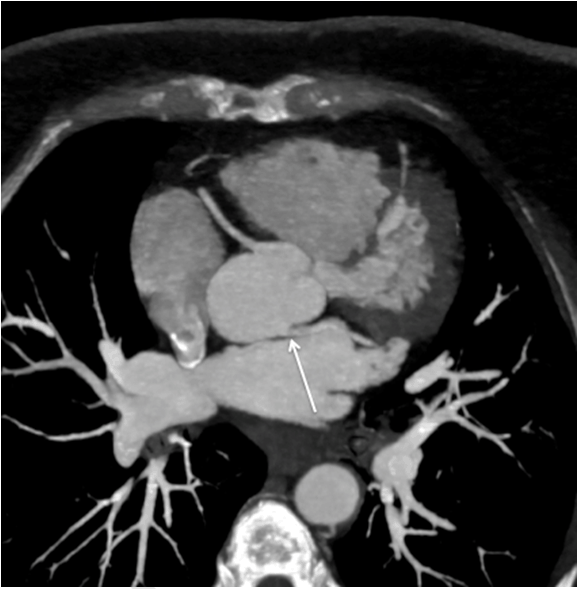

A contrast enhanced cardiac computed tomography angiography (CTA) was performed to further evaluate her symptoms and to investigate for a possible coronary artery disease. The computed tomography scan showed the left main coronary artery arising from the non-coronary sinus with an acute angle (LCANCS) (Figure 1). A nuclear exercise stress test performed and was normal (Figure 2).

Figure 1: Maximum intensity projection of cardiac computed tomography angiogram (CTA) showing anomalous origin of the left main coronary artery from the non-coronary sinus with acute angle take off (arrow) and oblique course behind the left coronary sinus.